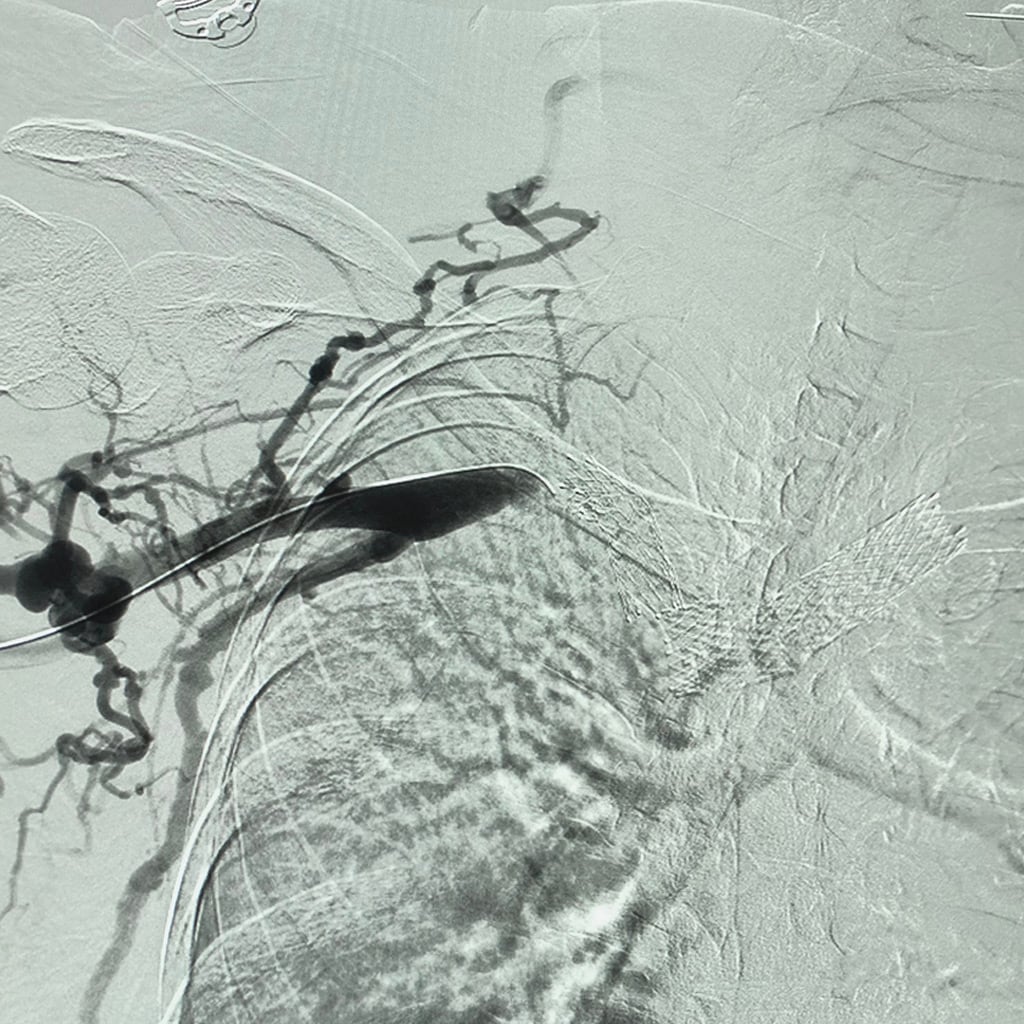

Peripheral angiography involves X-ray imaging and contrast dye to visualize blood vessels in arms, legs, and other peripheral areas. It helps identify narrowings, blockages, or other abnormalities that impede blood flow. By providing detailed information about the blood vessels’ condition, peripheral angiography aids in accurate diagnosis and treatment planning.